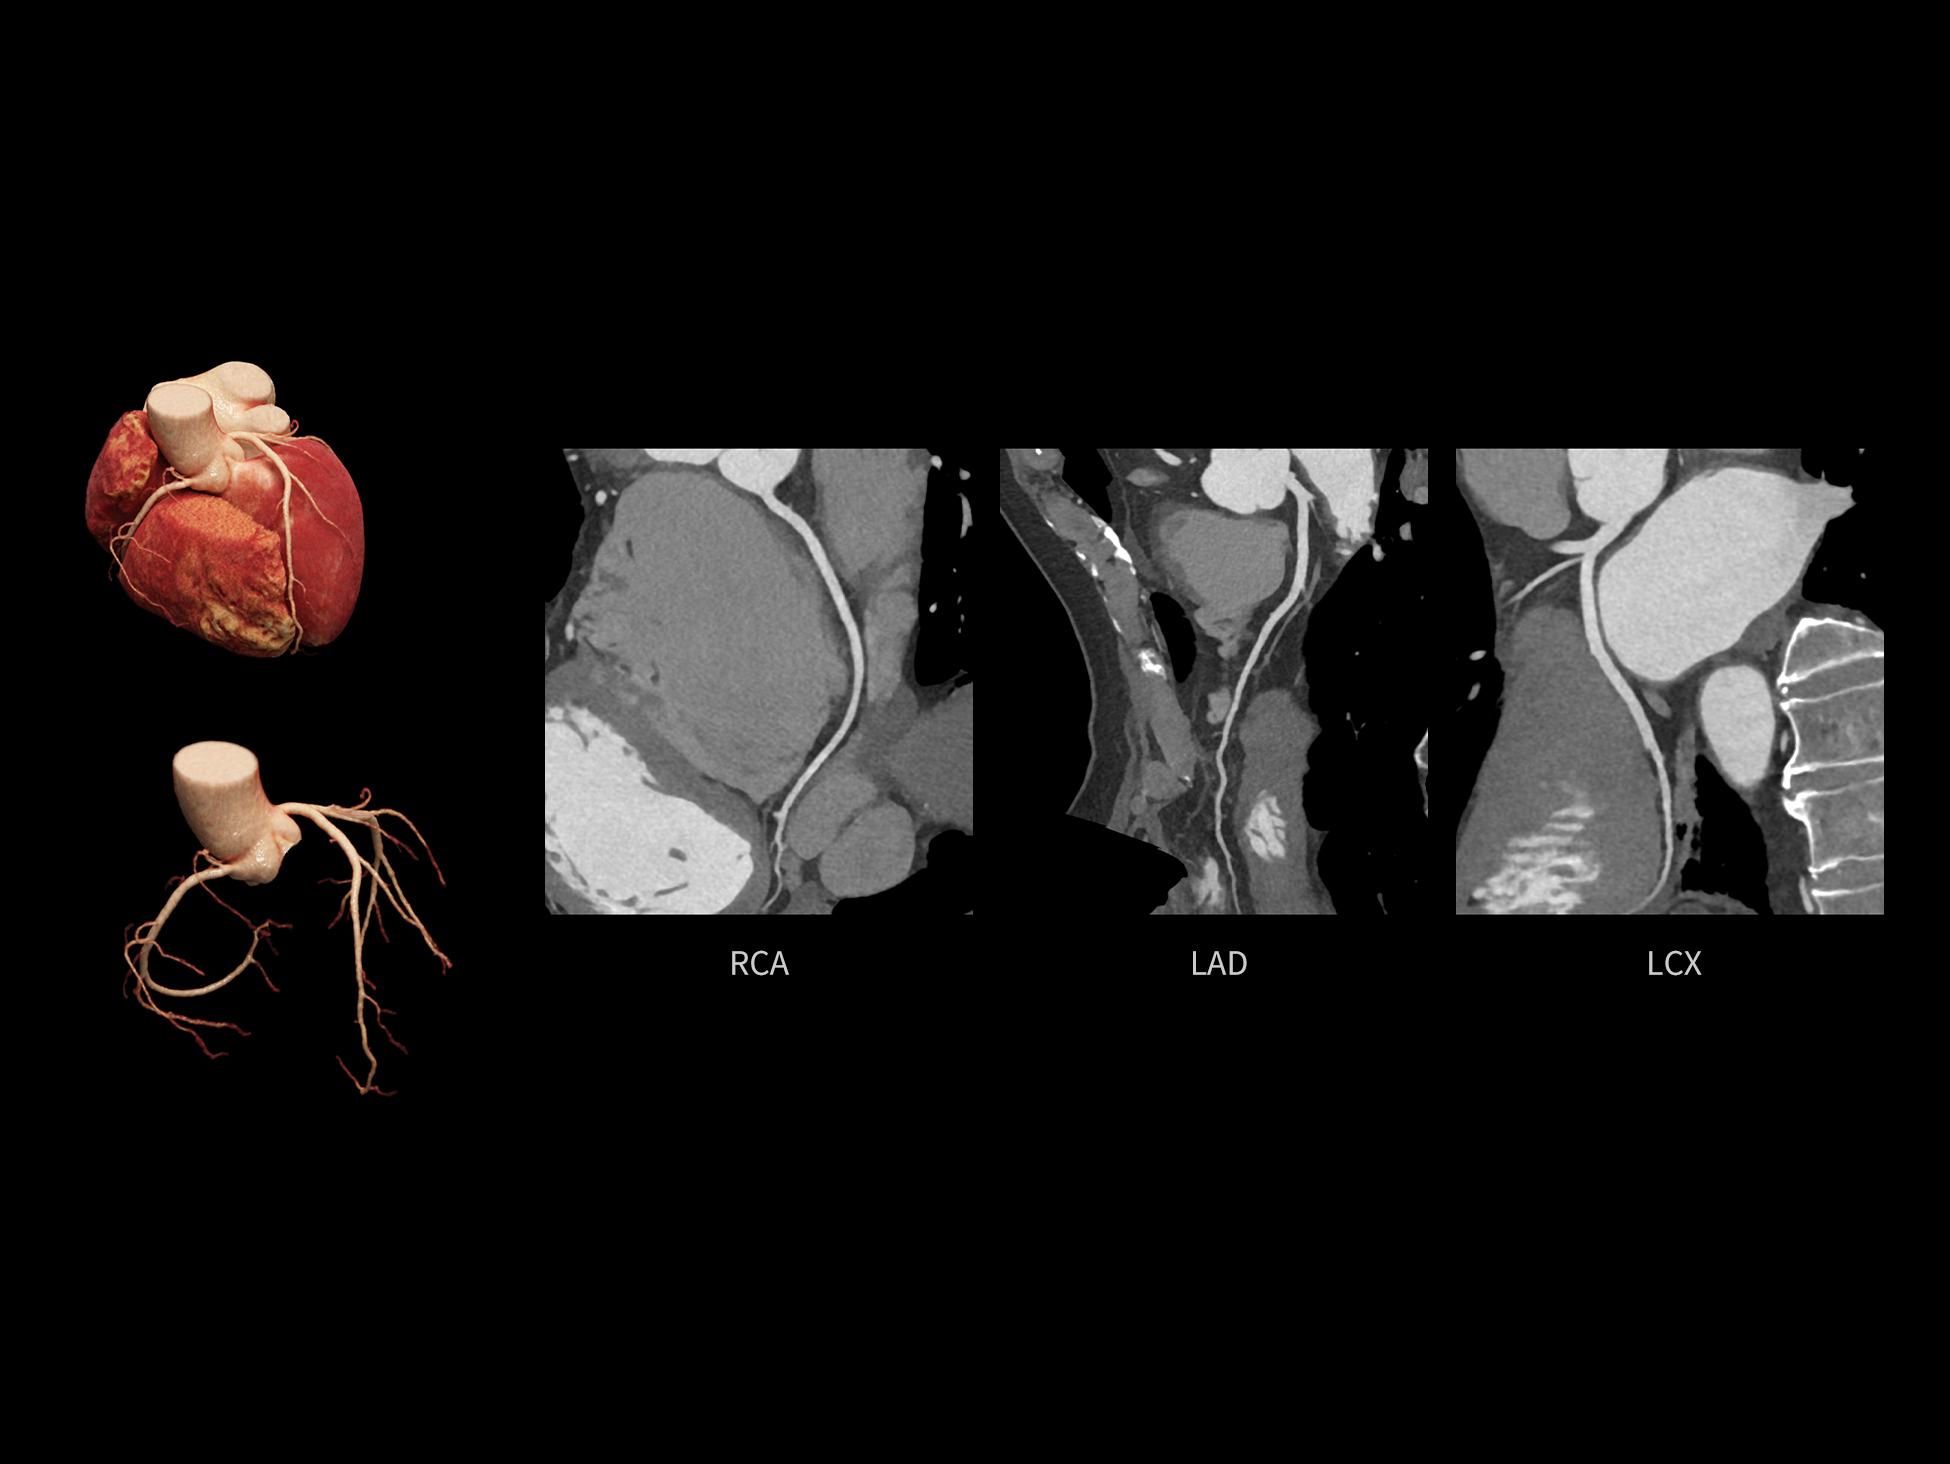

心脏成像,自由掌控

uCT SiriuX® 以 8ms 全心等效时间分辨率与16cm宽体覆盖,突破传统心脏成像局限,完整呈现搏动中的心脏结构与动态功能;配合无心电门控扫描与智能化工作流,更使心脏检查摆脱心率、配合度与操作复杂度的束缚,实现真正自由从容的成像体验,为临床功能评估提供更深层依据。

全心全时相高清成像

单心动周期内的任意时相获取高质量的冠脉CTA图像,确保稳定的心脏成像效果。

CardioCapture 2.0 可对心肌、瓣膜及心室等结构进行同步运动校正。基于深度学习的心脏精细分割,实现了更完整的心脏全局信息提取,能有效抑制全心运动伪影,显著提升心脏细节的清晰度与诊断可靠性。

全心结构运动校正